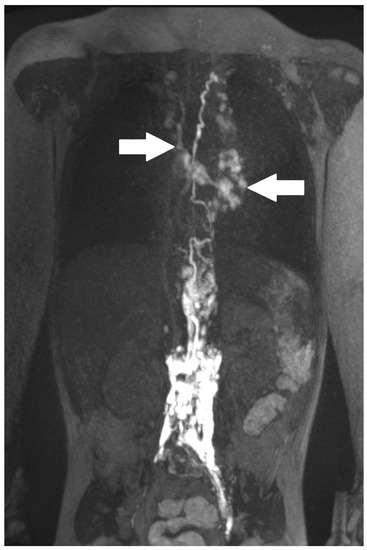

| 7 | 4 | increased signal neck, mediastinum and hilum, bilateral pleural effusion | TD intact, retrograde flow towards mediastinum and lung parenchyma bilateral | PLPS | TD bilateral TV 2 | CT revision, levosimedane | MCT diet, sandostatin, levosimedane | resolution (31/63/75)) |

| 8 | 3 | increased signal neck, axilla le > ri, mediastinum le > ri, pleural effusion | TD intact, retrograde flow to mediastinum, lung ri | PLPS | no fistula visualized | MCT diet | revision | resolution (22/42/50/19) |

| 11 | 3 | increased signal neck le > ri, mediastinum and hilum ri > le, pleural effusion | TD intact, retrograde flow towards mediastinum and hilum le | PLPS | no fistula visualized | diet modification | revision | resolution (42/62/71/20) |

| 12 | 4 | increased signal neck le > ri, mediastinum and hilum ri > le, pleural effusion ri > le, ascites | TD intact, retrograde flow towards mediastinum, hilum, lungs ri > le | PLPS | no fistula visualized | MCT diet, somatostatin | Glenn takedown | resolution (84/142/208/37) |

| 13 | 4 | increased signal neck, axilla, mediastinum, hilum and body wall, pleural effusion | retrograde flow towards hilum le, dermal backflow into thoracic wall | CLFD | TV 7–10 to hilum/ mediastinum | MCT diet | not performed yet | recurrent CT |